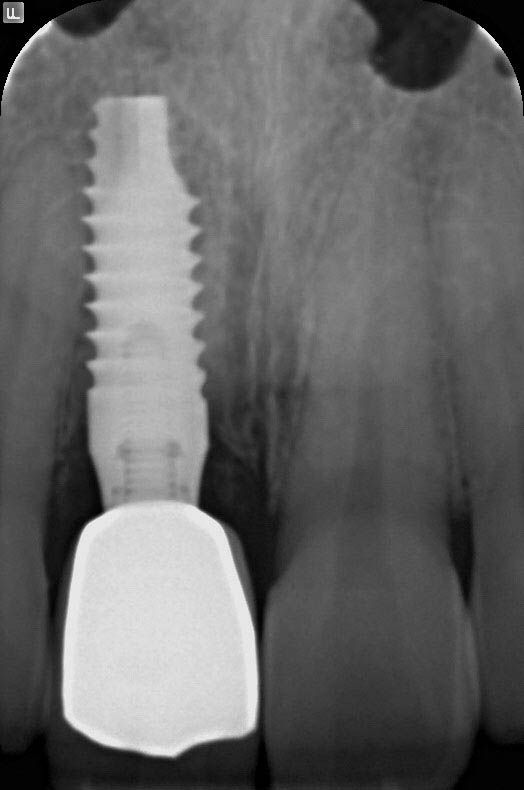

Control radiograph at 36 months: the stability of hard tissues is highlighted.